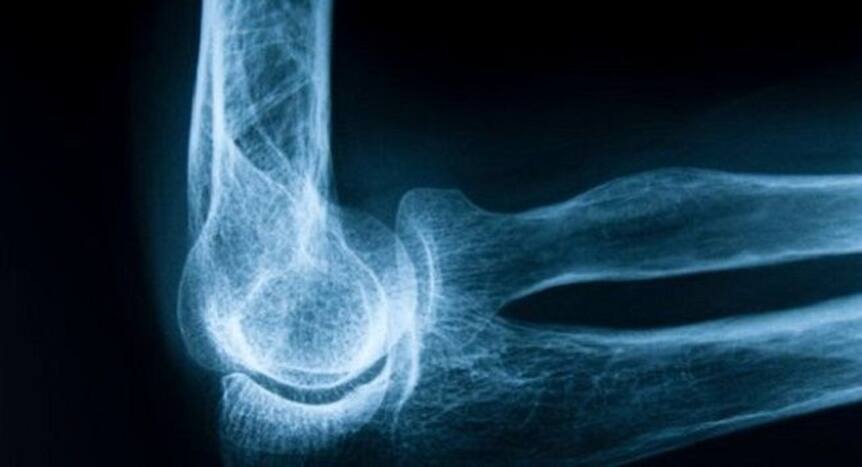

Risk factors of bone fracture you should know about

Bone fracture is basically the medical definition of a broken bone. It occurs when your bone is unable to take the pressure or physical applied on it. If you suffer from a bone fracture, you will experience intense pain in the affected part of your body and in some cases, you may faint from the pain it can cause. According to a new study published in the journal BMJ, researchers revealed that if you are suffering from chronic obstructive pulmonary disease (COPD), you are more likely to suffer from a hip fracture and every major osteoporotic fracture. While COPD increases your risk of getting a broken bone, there are other factors as well which may lead to a fracture. Here, we share with you risk factors that can cause a bone fracture.